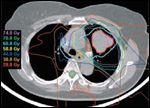

Dose distribution for a patient with stage III lung cancer treated with proton beam. Contours represent the lung tumor and involved nodes (red) and sub-clinically involved mediastinal nodes (light blue). Distribution shows the percent of the total dose. Beam arrangement includes a left lateral and posterior to the CTV (46 CGE) and a left posterior oblique to the GTV (30 CGE).

Even allowing for potentially confounding factors such as these, proton-beam dosimetry is an improvement over the use of photon beams (Fig. 2). The tissue-sparing capability of the proton beam is most apparent in the treatment of early-stage non-small-cell lung cancer (Fig. 3), but significant sparing also is achievable when protons are used to treat locally advanced disease (Figs. 4 and 5).

Studies are underway at Loma Linda that utilize proton beam radiotherapy in conjunction with chemotherapy for the treatment of locally advanced lung cancers. Neo-adjuvant and concurrent chemotherapy is administered with proton therapy, which is given as a concomitant boost. The dose to the sub-clinically involved mediastinum is 46 CGE in two CGE fractions with a GTV, BID boost of 30 CGE during the last three weeks of treatment. Despite the much larger target volumes in such cases, significant sparing of normal tissues still is achieved (Figs 4 and 5). In the most recent evaluation of ongoing results in 19 patients, no Grade 3 or 4 esophageal toxicities were observed; Grade 3 leukopenia was seen in two patients, and Grade 3 thrombocytopenia occurred in one individual.